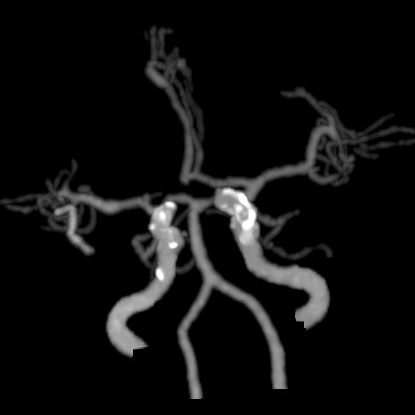

术前CTA:

CTA提示右侧大脑中动脉闭塞,左侧A1纤细。

延迟CTA扫描可见造影剂逆流至大脑中动脉主干。

CTA提示右侧颈总动脉迂曲,右锁骨下动脉与右颈总动脉成钝角。